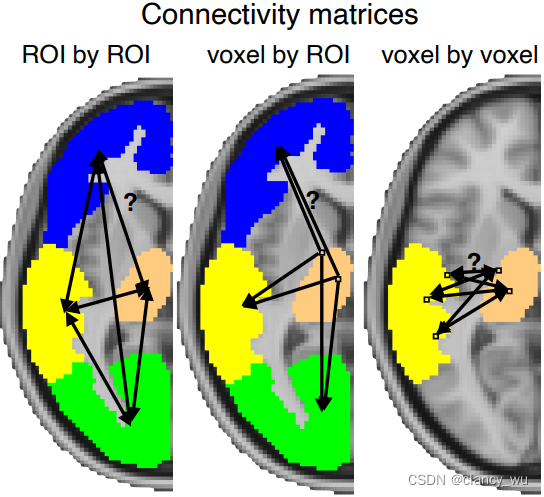

(五)structural-connectivity 结构连接

上面提了ROI的定量纤维束分析,其实还有种结构连接的分析,就是根据模板预定义的ROI,分析他们之间的纤维束连接。

3.ROI

ROI分析有两种,ROI-ROI和ROI-seed,即一种是两个ROI之间的structural connectivity,另一种是单个ROI中,所有穿过的纤维束。